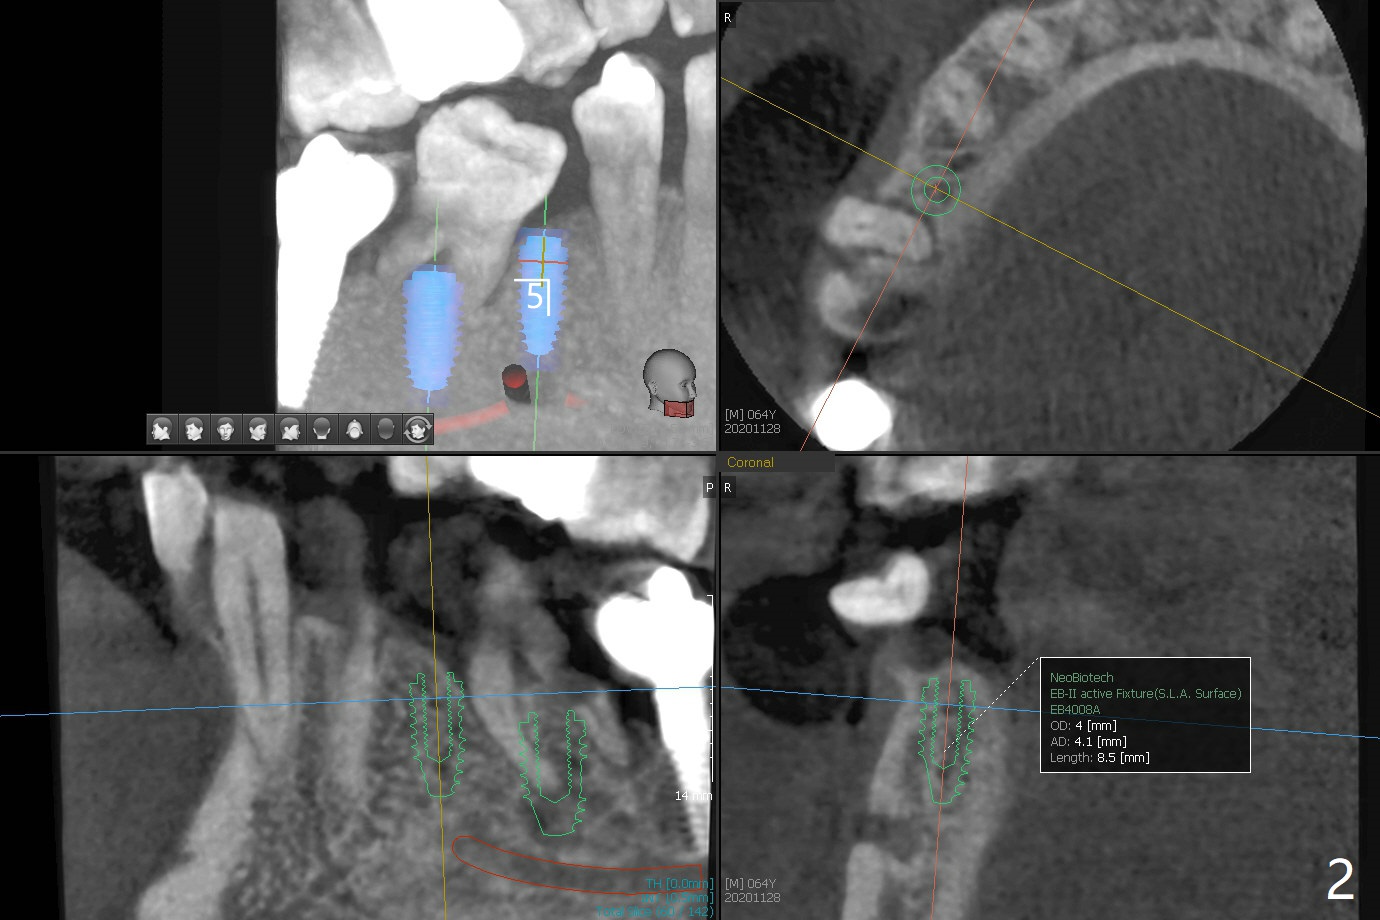

64岁男不注意口腔卫生,因为右上8颊侧颈部龋齿疼痛就诊拔除,也同意拔除右下6(远中颈部龋齿,图一:*),种植5,6(图一,二),如果扭力不是太差,即刻制作临时连冠,保护粘性骨粉,而且有利于马上提高口腔卫生(刷牙),也要求使用水牙线。伤口愈合后,牙冠分开,有利于龈乳头形成。